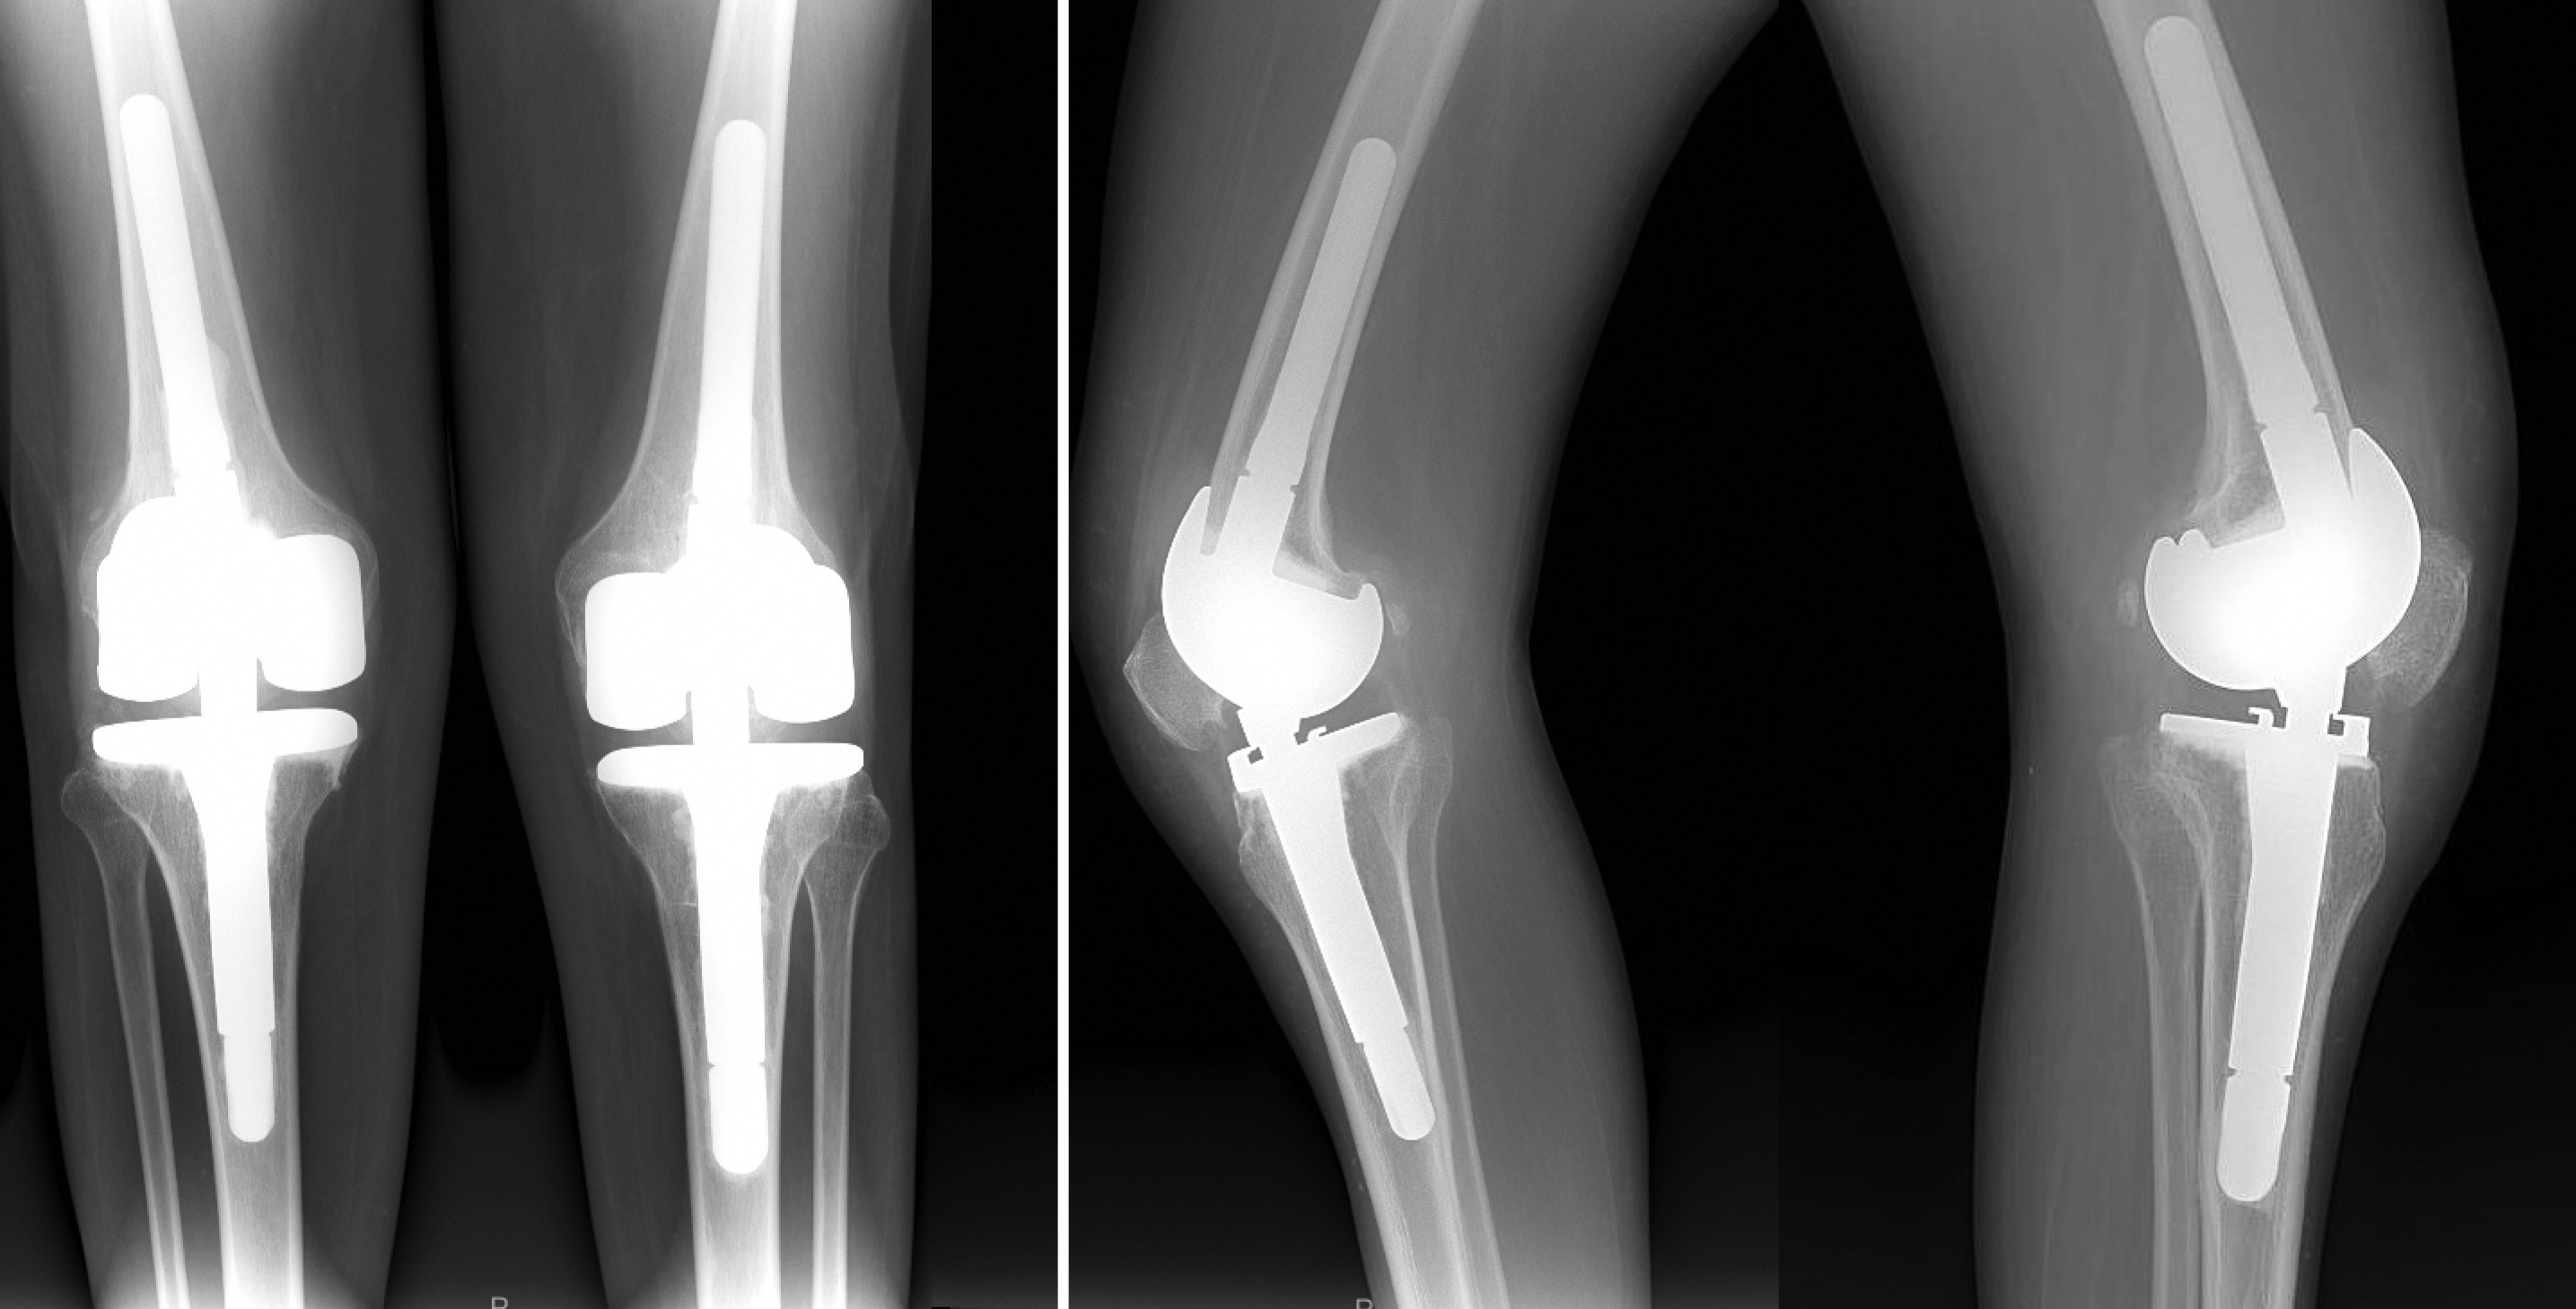

На момент написания данного материала сроки наблюдения составляли 4 года (рис. 11). Пациент ходит с полной нагрузкой. Амплитуда пассивных движений в обоих коленных суставах составляет около 130°. Рецидивов нестабильности и гиперэкстензии не наблюдается. В качестве дополнительной опоры пациент использует трость при длительных прогулках. Походка соответствует стереотипу для пациентов с гиперэкстензией вследствие перенесенного полиомиелита, однако он может передвигаться без дополнительной опоры в помещении.

Рис. 11. Ренгтенограммы через 4 года с момента второго этапа операции

Figure 11. X-rays taken over a period of 4 years after the second stage of the surgery

Субъективно пациент оценивает результаты проведенных операций как отличные. При оценке по опроснику KSS сумма баллов составляет 88, что также соответствует отличным результатам.

При попытке опоры на ногу без блокирования в положении гиперэкстензии пациент вынужденно падает ввиду нейромышечного дефицита. Однократно на сроке 6 мес. после второго этапа операции это привело к гемартрозу, краевому перелому надколенника. Пациент обратился за неотложной помощью — была выполнена лечебно-диагностическая пункция и рекомендована консервативная терапия, в том числе иммобилизация коленного сустава ортезом в течение 3 нед. На фоне проведенного лечения пациент вернулся к прежнему уровню двигательной активности.